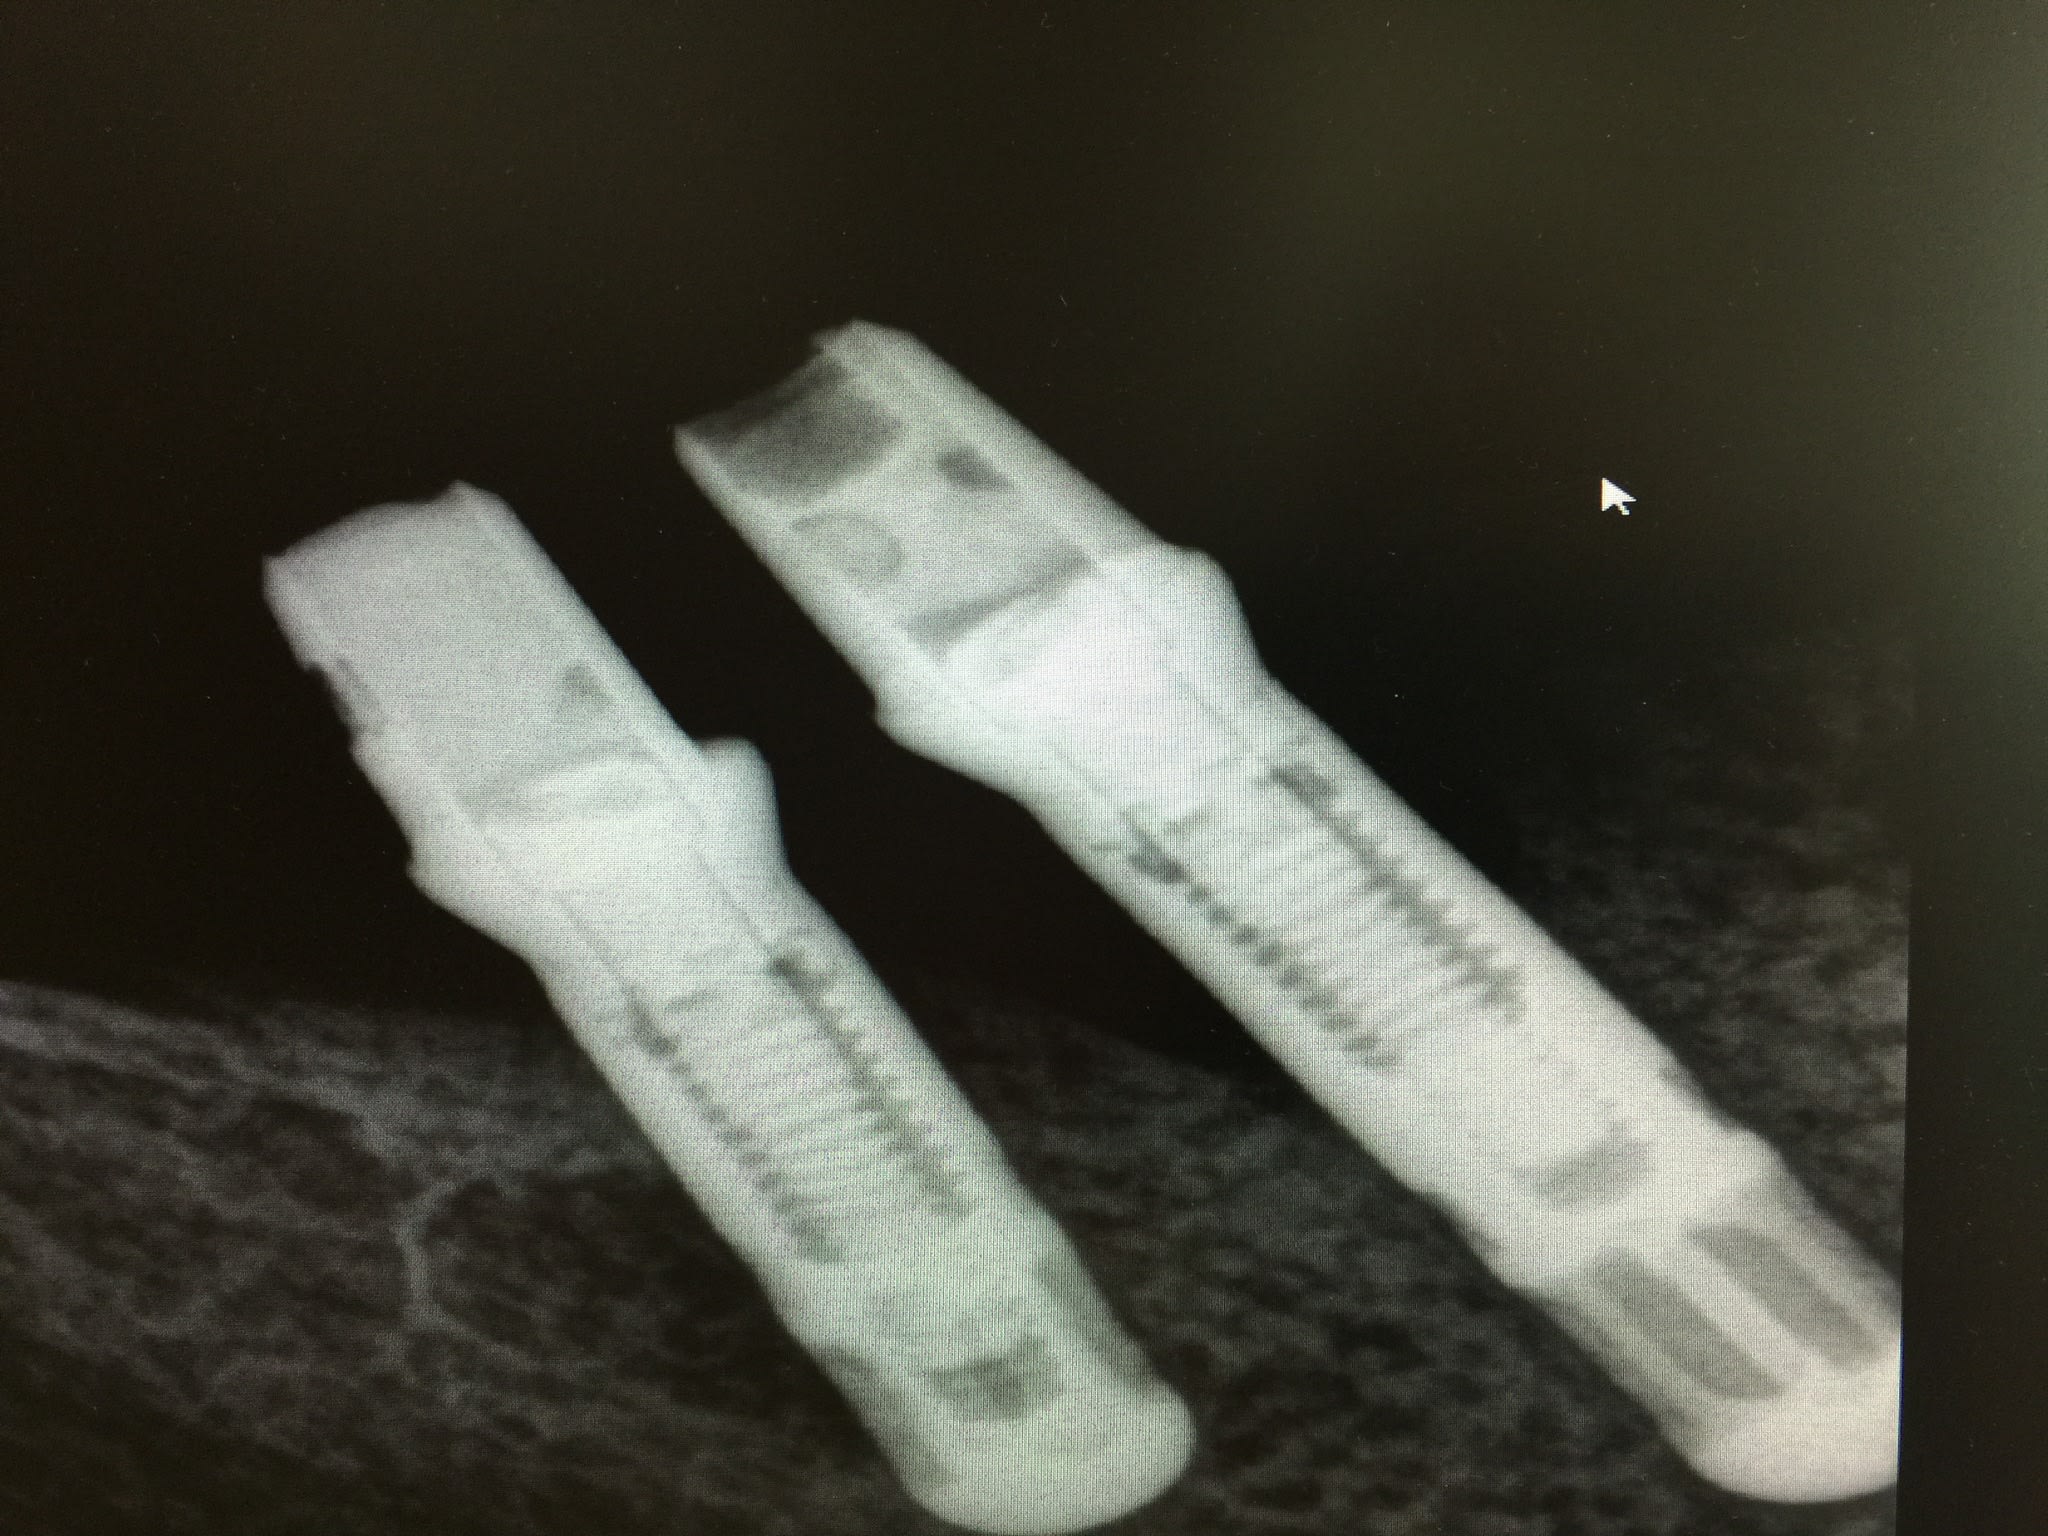

non...

avec le double filetage interne....ce sont des... camlog...;-)

http://whatimplantisthat.com/implant/cylinder-line-5/

http://osseosource.com/dental-implants/product_info.php?manufacturers_id=19&products_id=159

sûr que c'est du camlog...

pour le diamètre, c'est toi qui peut le dire en faisant une estimation avec la rétroalvéolaire....

amha c'est du 3.8 ou du 4.3...